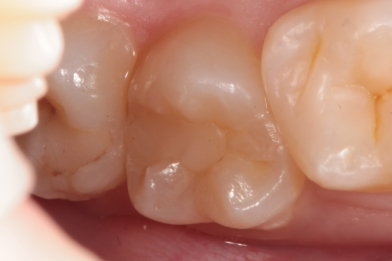

Жалобы на застревание пищи между зубами 26,25, реакция на сладкое и

Колиш Максим Петрович

холодное.

При осмотре обнаружен контактный кариес на зубах 26,25.

Лечений в один визит , восстановление функциональности композитной

реставрацией. -